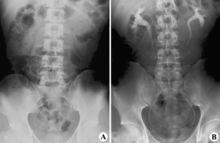

正常腹X線平片(A)和靜脈腎盂造影片(B)由於醫學設備的發展,磁共振成像(MRI)技術也可以使用2D、3D-TOF等特殊技術,利用泌尿系統內的尿液來實現只針對水的成像,無需逆行插管或是靜脈注射造影劑,就可真正實現無痛檢查。

急性腎盂腎炎一般不做IVP。慢性腎盂腎炎IVP注藥的X線徵象是腎盂腎盞的顯影時間延長,濃度減低,患者腎臟變小,腎實質呈局限性萎縮,以腎皮質變薄為主或有腎外緣局部凹陷,伴有鄰近的腎盞變鈍或呈鼓槌狀等變形;腎盂有時也可變形,有擴大積水現象。